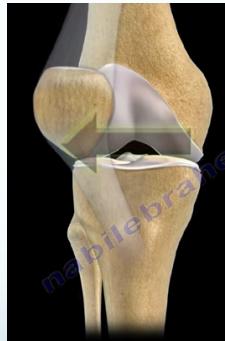

Patellar Dislocation

- More common in adolescent females

- Genu valgus results in pulling patella laterally

- Sudden Quadriceps pull in sports

- May spontaneously reduce

- Self reduction: Reduction easy by itself when patient contracts quadriceps

- Surgery if recurrent

Risk Factors for Recurrence:

- Ligament laxity

- ↑ genu valgum = ↑Q Angle

- High patella